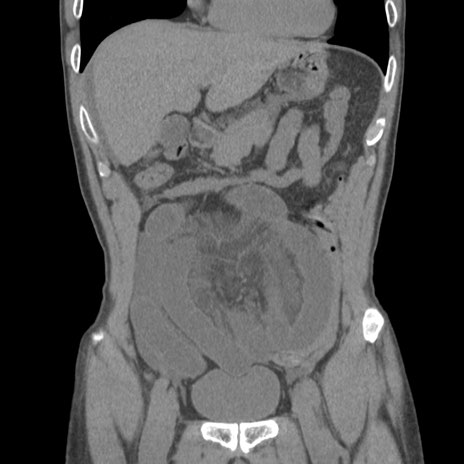

症例56 CT(冠状断像)

横断像